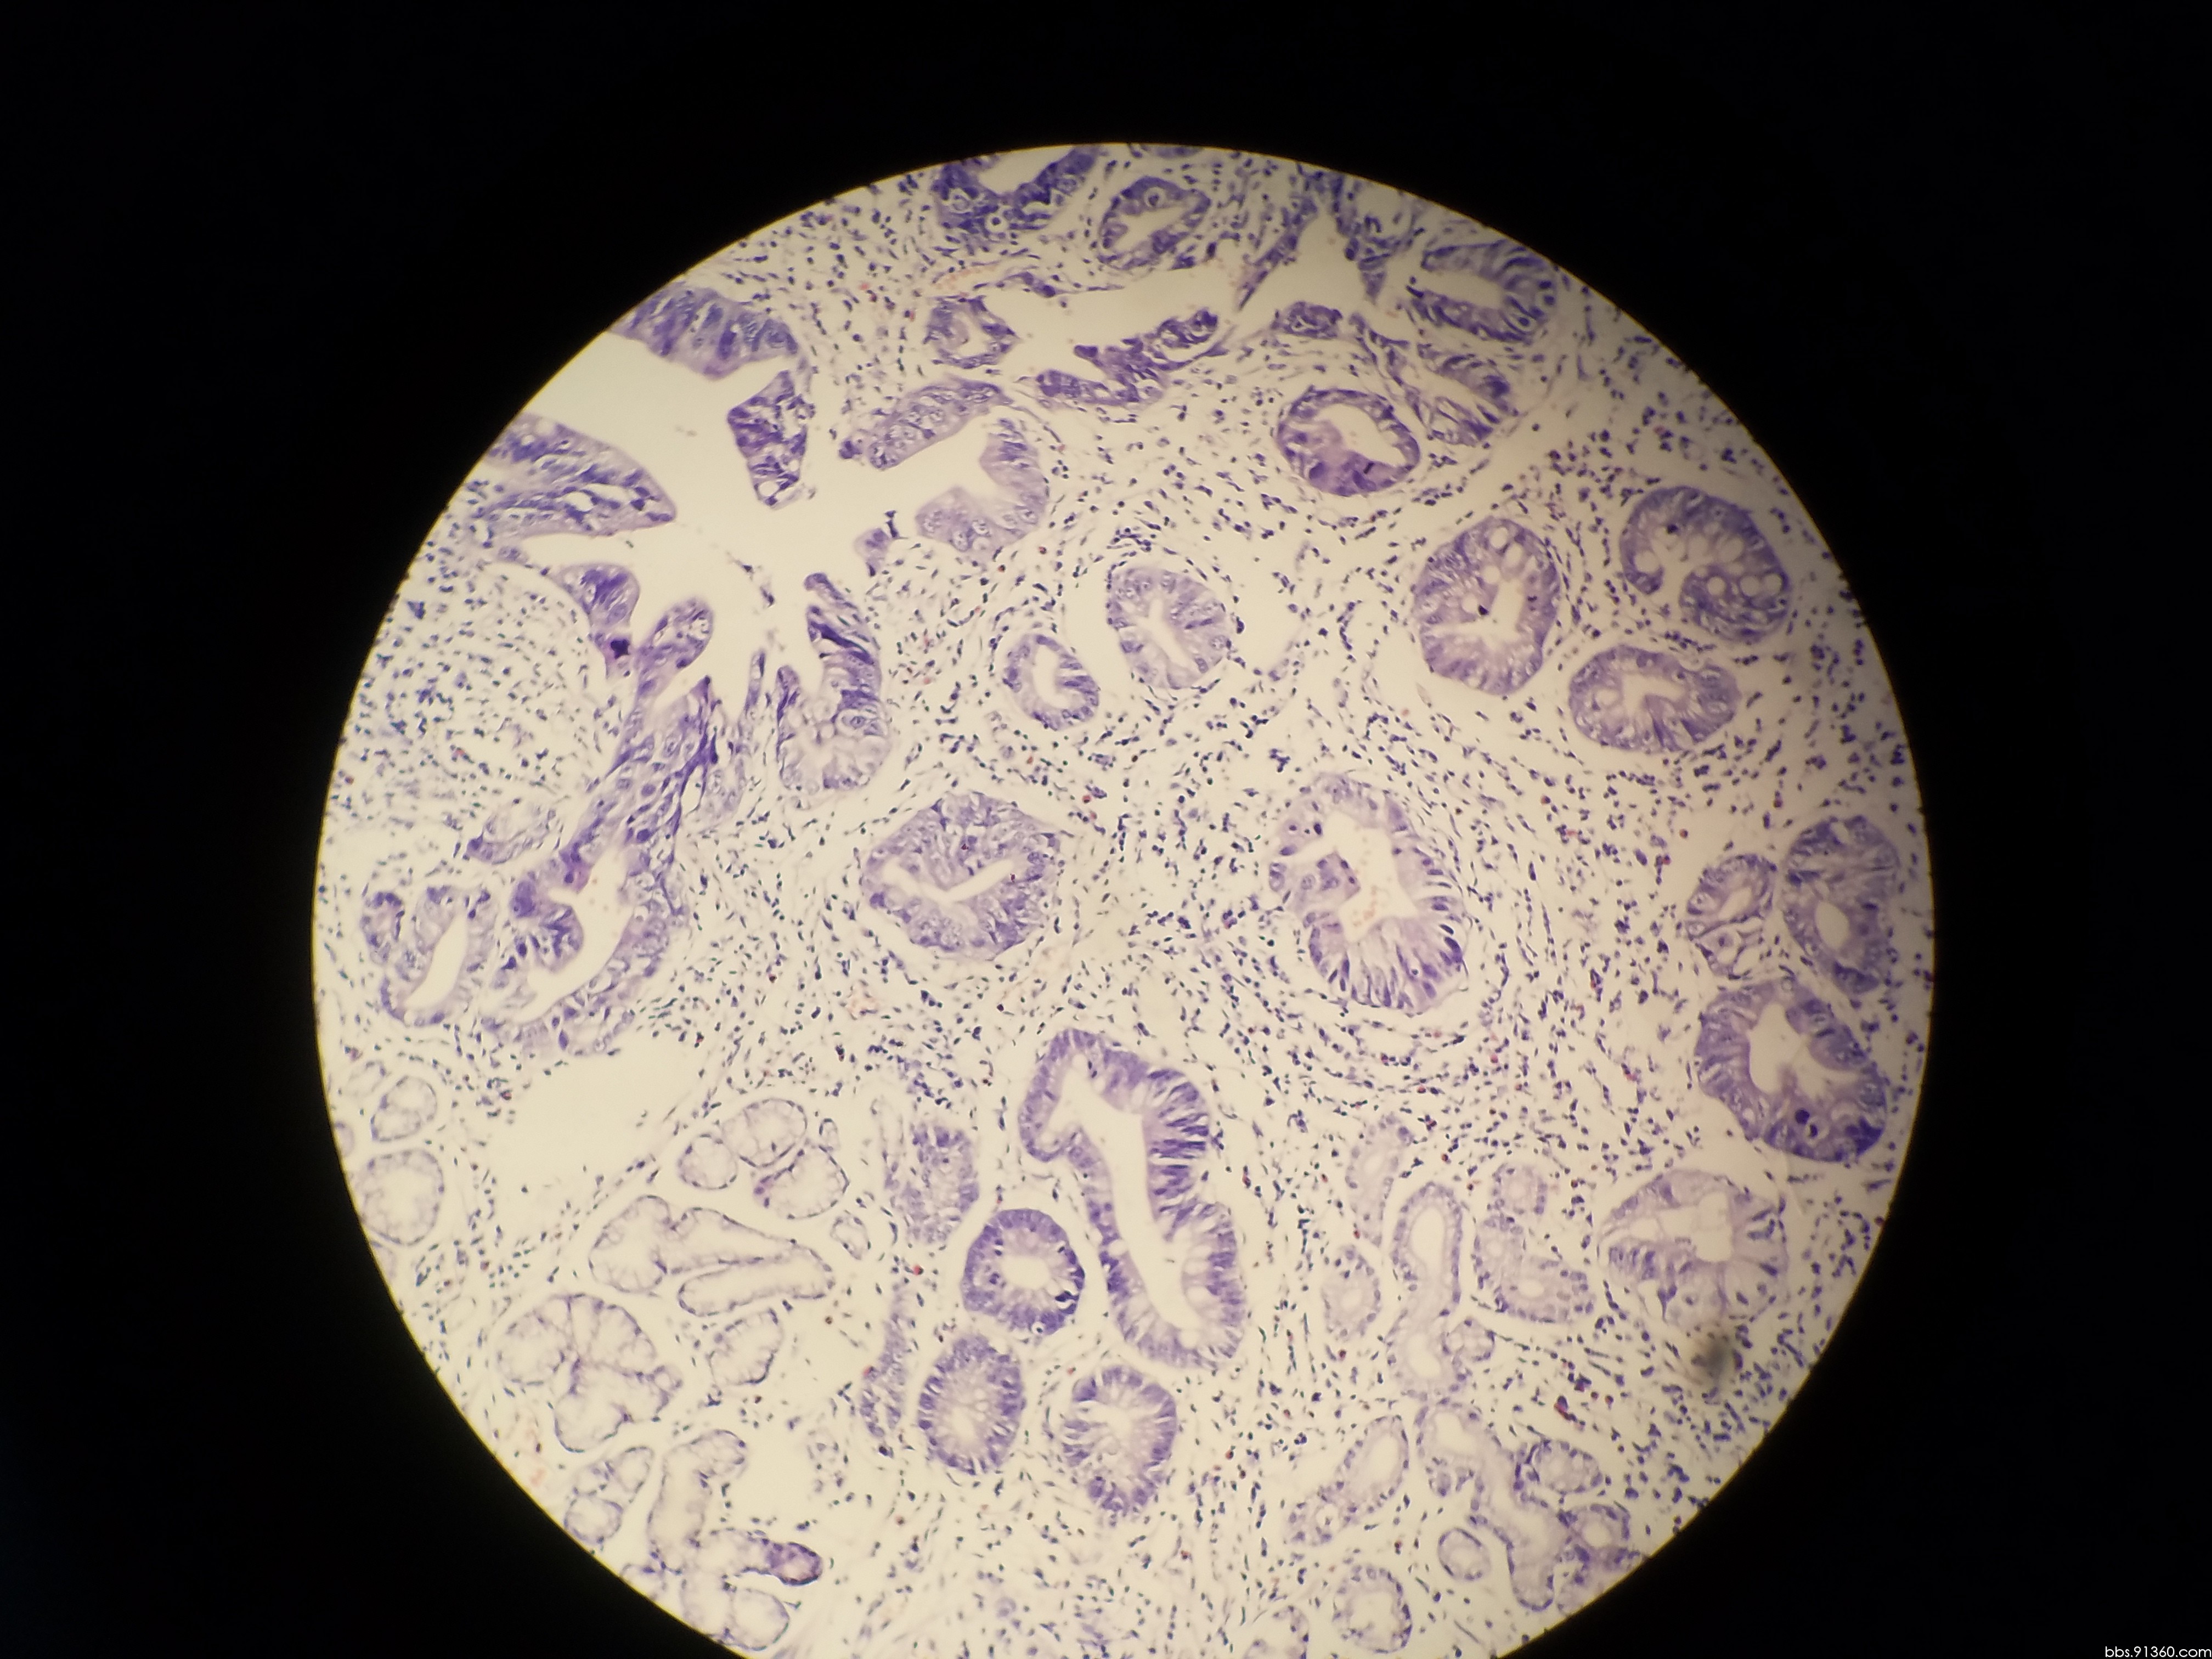

胃窦部黏膜组织活检镜下如图所示胃黏膜发生的有关病变的描述

胃窦部黏膜组织活检镜下如图所示胃黏膜发生的有关病变的描述错误的是

胃窦部黏膜活检

胃窦部黏膜活检

胃窦部黏膜活检

胃窦部黏膜活检